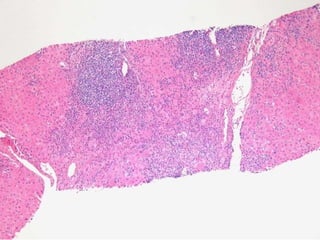

BS09-10453 55 yo, female.  Clinical history:  Elevated ALT/AST. Viral serologies negative.

BS09-10453:  Dx: Chronic hepatitis, with severe activity (bridging necrosis) and portal fibrosis, ? autoimmune hepatitis vs. drug/toxin mediated injury. Corresponds to: Modified Ishak stage 1/4 Metavir F1

BS09-10453 55 yo,female. Clinical history: Elevated ALT/AST. Viral serologies negative.

BS09-10453: Dx:Chronic hepatitis, with severe activity (bridging necrosis) and portal fibrosis, ? autoimmune hepatitis vs. drug/toxin mediated injury. Corresponds to: Modified Ishak stage 1/4 Metavir F1